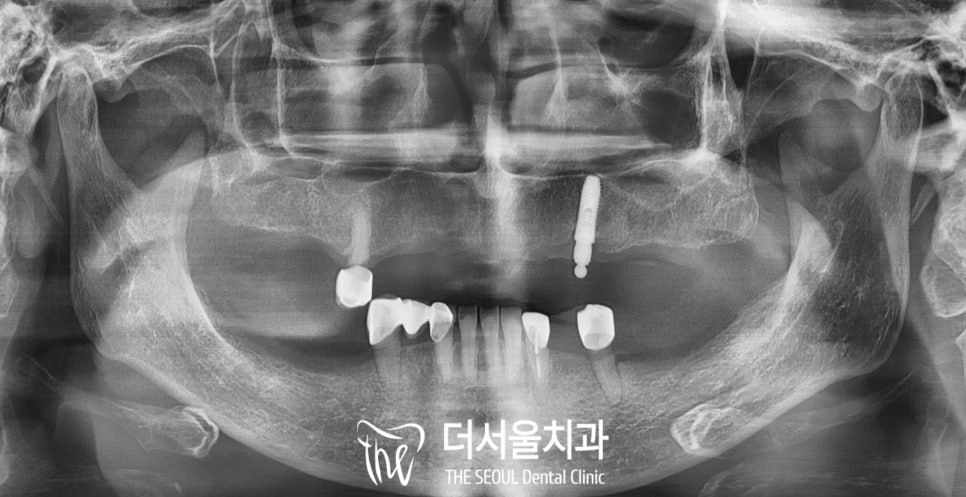

구강을 살펴보면

오래된 틀니 사용으로

치조골이 많이 얇고 낮아져있습니다.

또한 부분틀니를 걸어 사용할

남아있는 자연치들도

어느 정도 수명을 다한 게 느껴질 정도로

흔들림이 있었습니다.